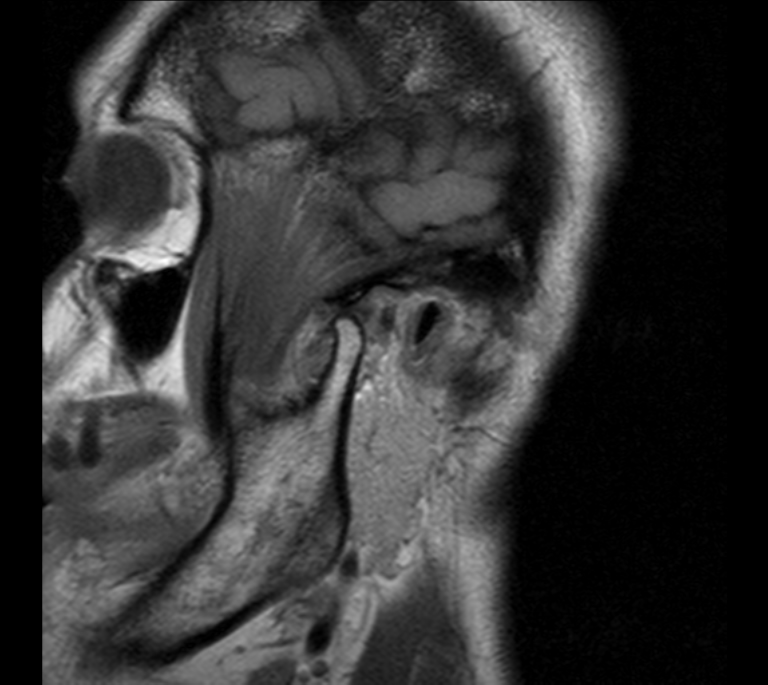

RM Partes Blandas

Prueba diagnóstica no invasiva que consiste en la obtención de imágenes de alta definición anatómica del cuello mediante el empleo de un campo electromagnético y ondas de radio (con un emisor y un receptor). No utiliza radiación ionizante. Indicaciones: sospecha de tumor, infecciones, ganglios.